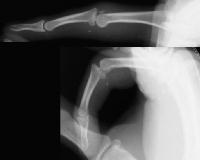

Clinical Example: Hamate osteochondral graft for PIP fracture dislocation

Dorsal fracture dislocations of the proximal interphalangeal joint are a common and difficult injury. The seriousness of the problem is often underestimated by the patient, leading to delay in treatment. Even when treated early, these fractures are difficult because the joint surface is crushed into small pieces. Many treatment options exist, none perfect. A new approach for these fractures involves replacing the destroyed section of the joint with an osteochondral graft taken from the dorsal hamate, where the shape of the joint surface matches that of the base of the middle phalanx. This is an example of this technique.

This gentleman injured his ring finger almost two weeks ago playing football, and has continued playing with the finger buddy taped. The distal interphalangeal joint has not bent for years following a different prior injury.

Xrays show a comminuted dorsal fracture dislocation of the proximal interphalangeal joint with dorsal subluxation.

The joint moves, but through an unnatural hinging on the edge of the fracture.